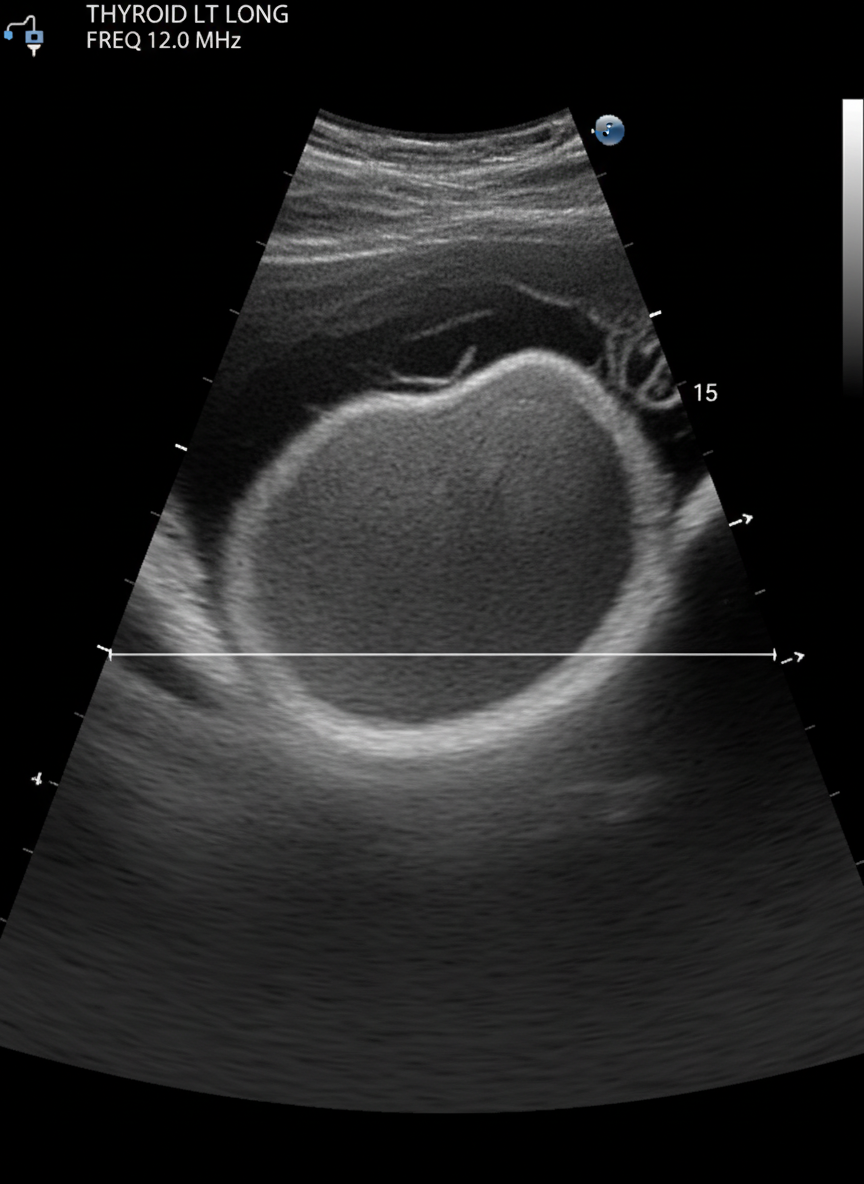

그 다음으로는 갑상선 초음파 검사를 하게 되는데,

이 초음파 검사를 통해

갑상선 결절의 유무와 크기, 모양 등을 확인할 수 있답니다.

초음파는 통증도 없고 아주 간단한 검사라서

부담 없이 받으실 수 있을 거예요.

만약 초음파 검사에서

의심스러운 결절이 발견된다면,

미세침 흡인 세포 검사(조직 검사)를 진행하게 돼요.